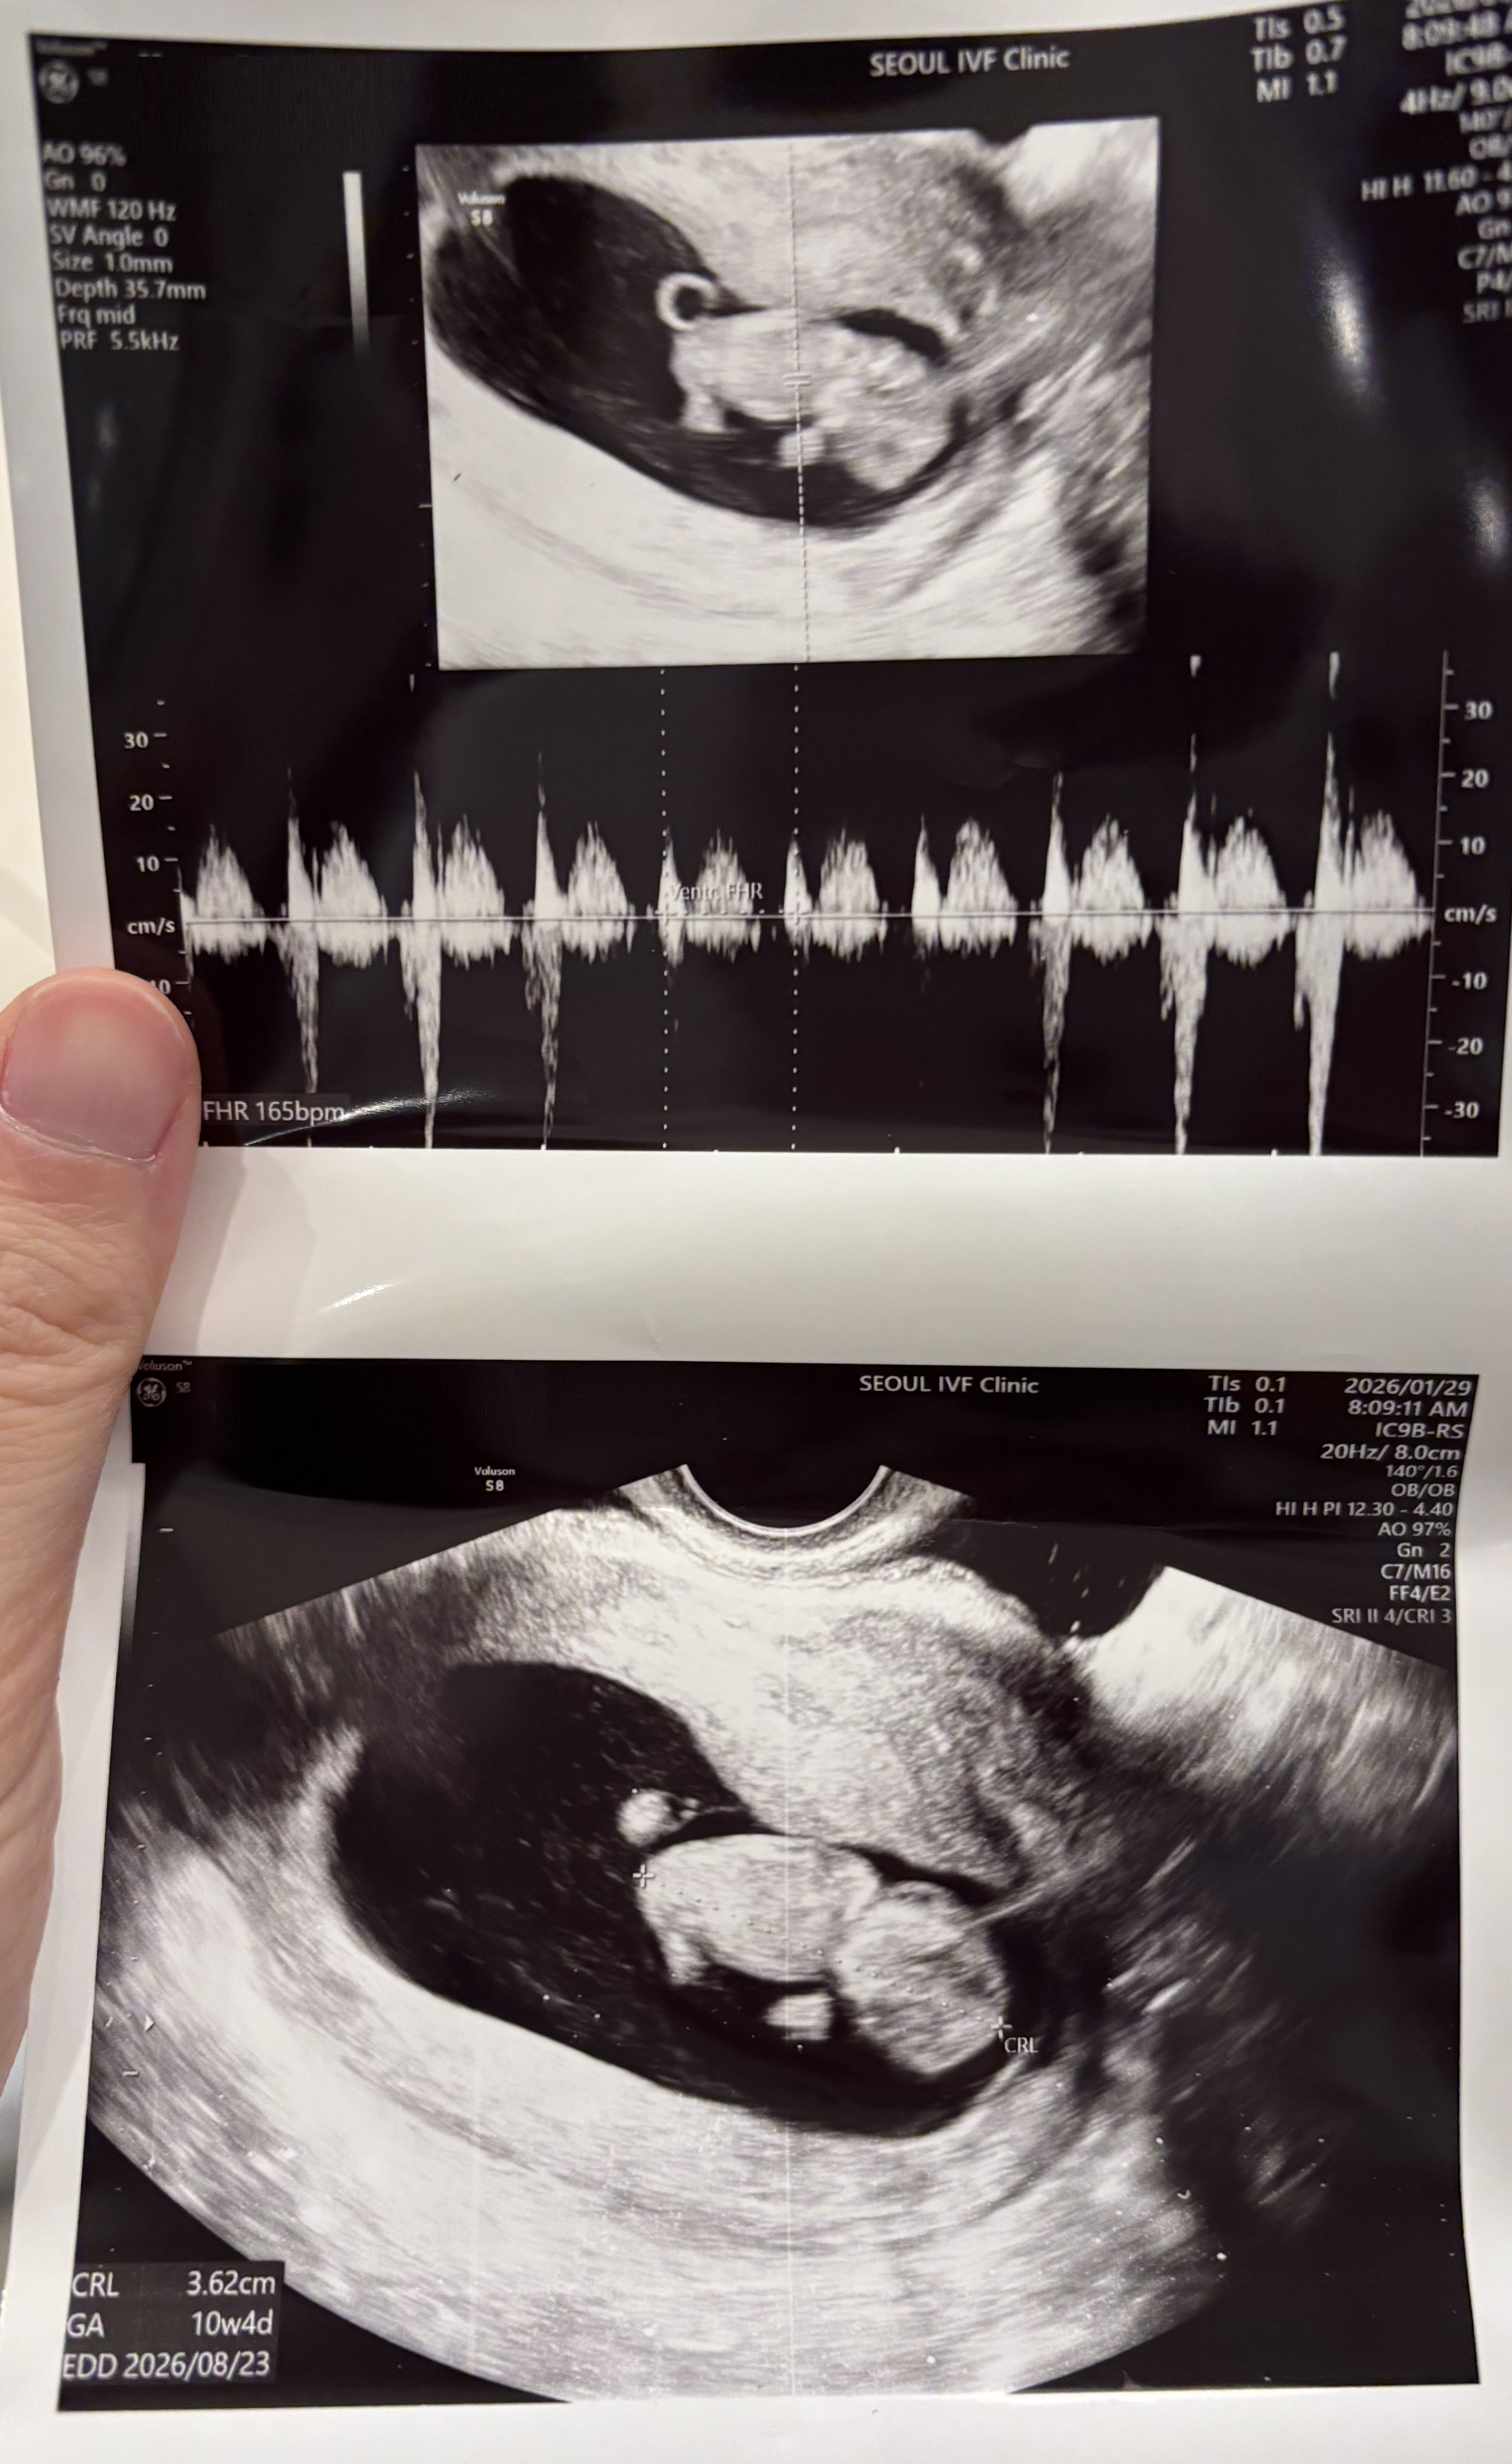

| 가슴 떨리는 임신 이야기를 공유해 주세요. | 동결 3차 시도 끝에 임신에 성공하여 드디어 10주차에 진입하게 되었습니다. 이번에 실패해도 다시 채취를 해야겠다고 마음먹었었지만, 기대반 불안반을 안고있던 때 선물처럼 아기가 찾아왔습니다. 더욱 소중하게 느껴집니다. |

| 치료 도중 느꼈던 가장 기뻤던 순간과 절망적인 것들은 무엇인가요? 잊지 못할 경험이 있나요? | 가장 기뻤던 순간은 아기의 심장 소리를 들었을 때였고, 가장 힘들었던 순간은 이식 8일차에 hCG 수치가 낮게 나왔을 때였습니다. 마음을 졸이며 지켜보던 시간이었지만, 아기가 건강하게 잘 자라주어 더욱 감사한 마음이 들었습니다. |